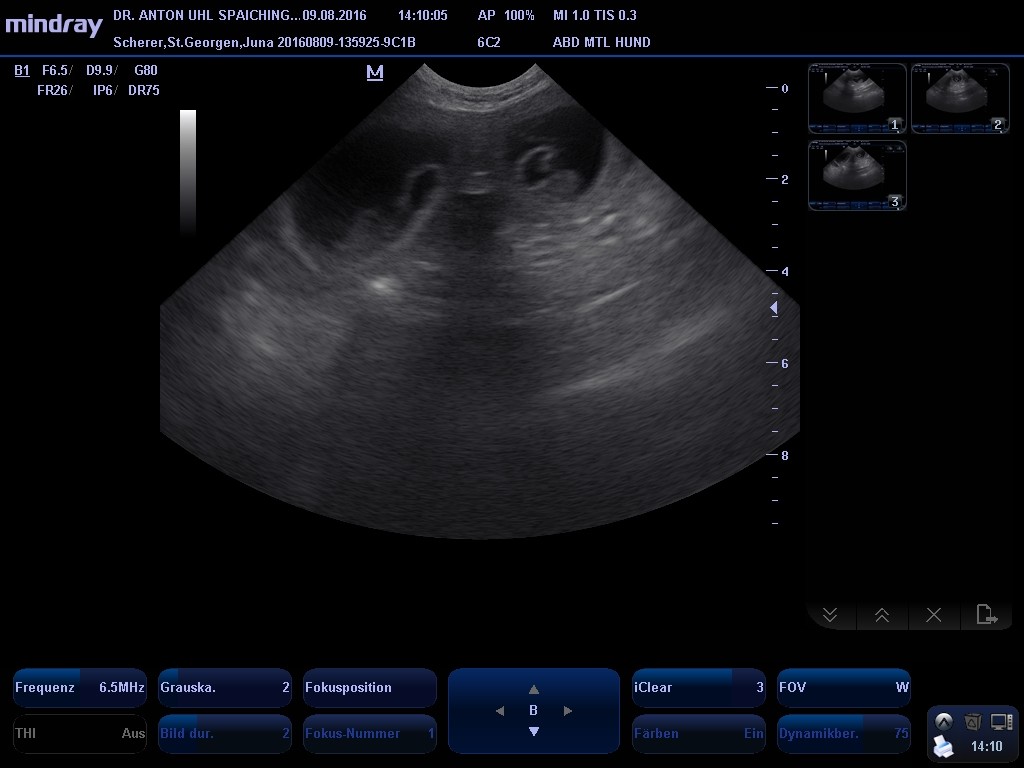

Am 9.8.2016 waren wir mit Yuna beim Ultraschall. Jetzt ist sie erste spannende Zeit des Wartens vorbei :-) Yuna und Da-chu werden Eltern. Wir sind sehr glücklich. Nun hoffen wir dass die Schwangerschaft auch weiterhin gut verläuft und wir uns um den 10.September über Babys freuen dürfen.